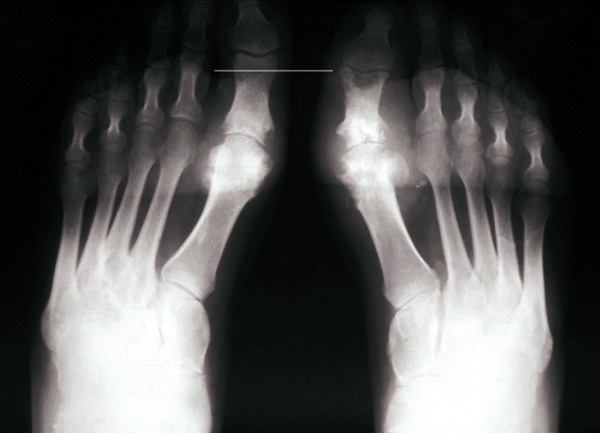

Les radiographies permettent de déceler des modifications ostéocartilagineuses asymétriques (mains, pieds, poignets, coudes, genoux), secondaires à la réaction inflammatoire autour des tophus, comportant :

• des érosions osseuses initiales caractéristiques : encoche épiphysaire (fig. 3) avec un éperon osseux (aspect en hallebarde) ;

• une image d’empreinte dans les parties molles (augmentation de la densité des parties molles dues au tophus) très évocatrice (fig. 4) ;

• un interligne longtemps conservé (contrairement aux autres rhumatismes destructeurs) [fig. 3] jusqu’au stade de goutte chronique et l’absence de raréfaction osseuse périarticulaire permettant de différencier la goutte d’autres arthropathies ; à un stade avancé, la goutte tophacée peut avoir un potentiel destructeur à la fois articulaire et osseux (fig. 4).

La forme pseudorhumatoïde est rare (5 %), simulant une polyarthrite rhumatoïde. L’arthrite chronique à PPC se présente comme une oligo- ou une polyarthrite, avec parfois des signes systémiques d’inflammation (élévation de la vitesse de sédimentation et de la protéine C-réactive [CRP]). La superposition d’accès aigus microcristallins est évocatrice de ce diagnostic. Il s’agit d’un diagnostic différentiel de polyarthrite rhumatoïde du sujet âgé ou de pseudopolyarthrite rhizomélique. Le diagnostic repose sur la mise en évidence des cristaux de PPC, même si les radiographies standard sont évocatrices. L’atteinte radiographique associe des calcifications des cartilages articulaires (fig. 7) et des fibrocartilages (fig. 8, 9, 10 et 11) [à rechercher systématiquement sur les radiographies de poignets, genoux et symphyse pubienne]. La mise en évidence d’une chondrocalcinose sur des radiographies standard renforce le diagnostic de rhumatisme à PPC mais l’absence de dépôts calciques ne l’élimine pas (la sensibilité de la radiographie standard étant imparfaite). L’échographie peut mettre en évidence des dépôts de PPC, qui apparaissent comme une fine bande hyperéchogène au sein des cartilages hyalins et comme des points scintillants dans les fibrocartilages ou dans la membrane synoviale. La sensibilité de l’échographie est bien supérieure à celle de la radiographie standard. Le scanner peut également mettre en évidence des dépôts calciques évocateurs, notamment au niveau du rachis ou du bassin qui sont plus difficilement explorés par les radiographies et l’échographie.